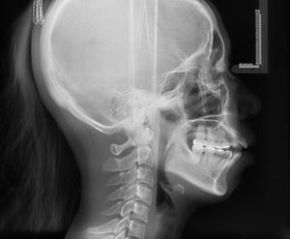

Bezdyskusyjną gwiazdą pikniku będzie aparat rentgenowski i jego „dzieła”. Podczas I wojny światowej Maria Skłodowska- Curie była szefową służby radiologicznej w Francji, organizowała ruchome ambulanse oraz punkty rentgenowskie. W sumie wykonano w nich prawie milion sto tysięcy prześwietleń. Podczas pikniku sprawdzimy, gdzie nas „dotknęła Maria” – zachęcamy do przynoszenia niepotrzebnych zdjęć rentgenowskich, z których wspólnie stworzymy artystyczną instalację.